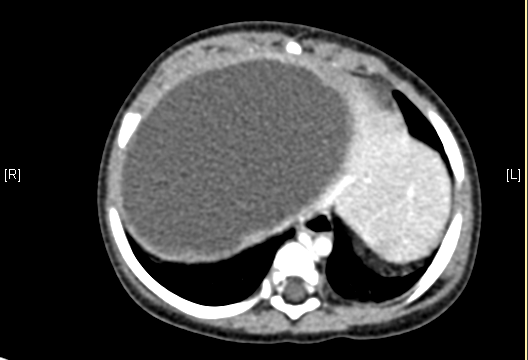

上腹部增强CT:肝右叶囊实性占位。上腹部增强CT示间叶性错构瘤。

术前CT检查:

静脉期